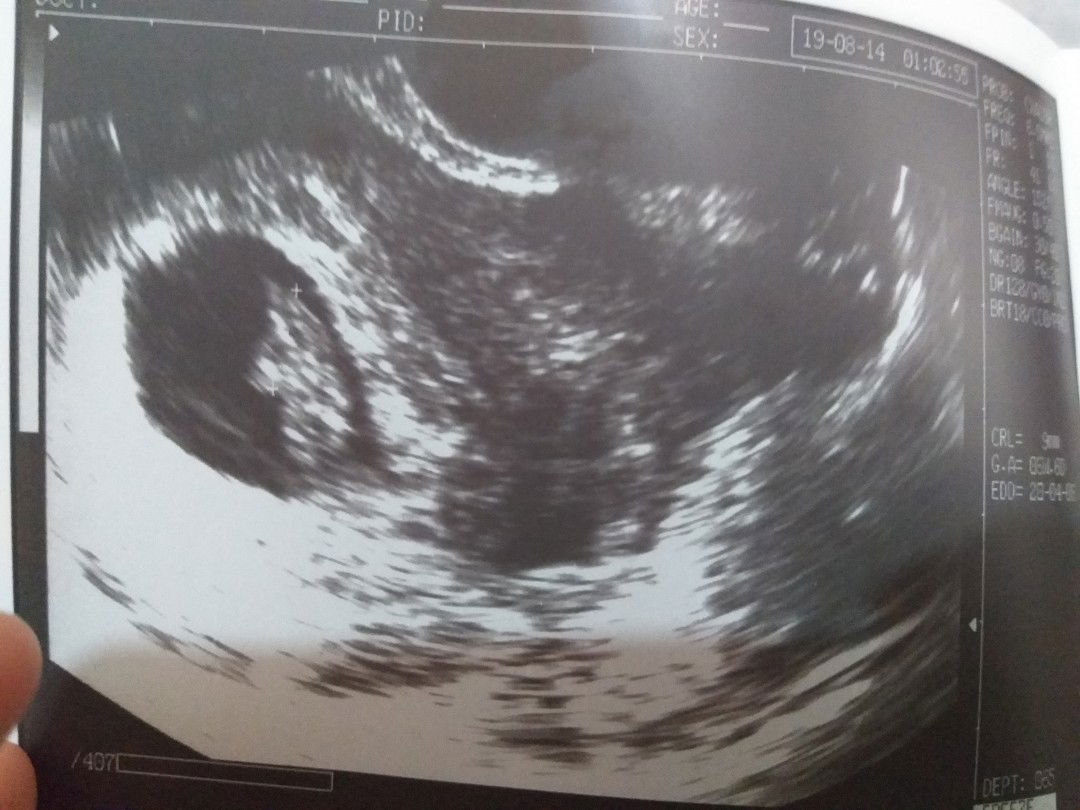

mono amniotic twins

Good day mga sis..nagpa checkup ako today and ndi ko alam kung anong mararamdaman ko... 1st baby ko po..mixed emotions kc ung baby ko dw po monoamniotic twins...1 placenta at 1 sac lng cla.. Maxado dw pong rare ung ganito.. Sabi kc ng doctor,its posible dw na ung isa matunaw ng kanya..or mamatay ung isa,at ung isa mabuhay which is ndi ok kasi may patay sa loob..and posible dn dw mawala parehas or mabuhay parehas.. Ndi ko tlga alam mararamdaman ko kc sobrang gusto kong mgka babay..super laking blessing but iniisip ko ung health nila and sana maging normal..? Mga sis,please pray for us..thanks.. Just sharing bcoz ndi ko tlga alam mararamdaman ko..? Thanks..